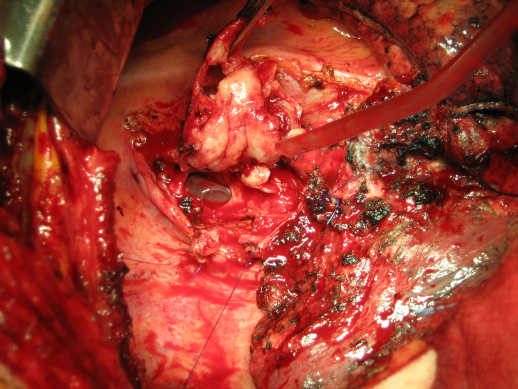

Meistens liegt jedoch ein ossärer Befall eines extrathorakalen Tumors vor. Beispielsweise Metastasen eines Hypernephroms oder eines Mamma-Karzinoms, welche noch nach einer Latenzzeit von vielen Jahren auftreten können. In unserem Kollektiv trat einmal nach 20 bzw. 28 Jahren nach Mamma-Ablatio eine Thoraxwandmetastase (Abbildung 8 [Abb. 8]) auf.

Abbildung 8: Infizierte Mammakarzinommetastase